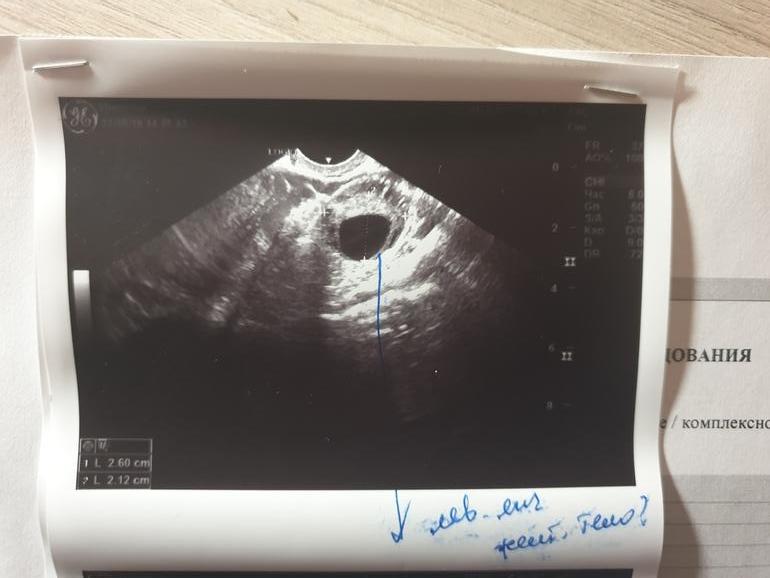

Девочки, может кто из вас разбирается в УЗИ, фото прикрепляю, была на 19д.ц. цикл у меня обычно 28 -30дней в Л.Я увидела ЖТ 21мм, но почему то поставила его под вопросом, хотя вроде опытный гинеколог делала, и вот теперь не могу понять, могла ли она перепутать ЖТ и фоликул? Сегодня уже 33д.ц, на 30 тест был отриц. Предвестников М никаких, обычно живот сильно ноет перед ними...

Это фолликул скорее всего,а не жт ,у жт края размытые как клякса,а тут четкие,а задержка,потому что овуляции не было,поздняя очень будет,судя по узи

Вообще то на УЗИ снимке фоликул доминатный. Желтое тело выглядит совсем иначе, края не четкие и цвет немного другой. Врач вообще у вас жесть